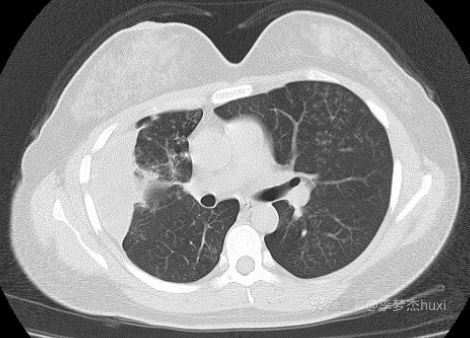

主诉:1月前体检发现右侧包裹性胸腔积液,肺部无异常,未进一步诊治。一月后复查除了包裹性胸腔积液外,肺内增加了多发结节影。无发热,无呼吸道症状。